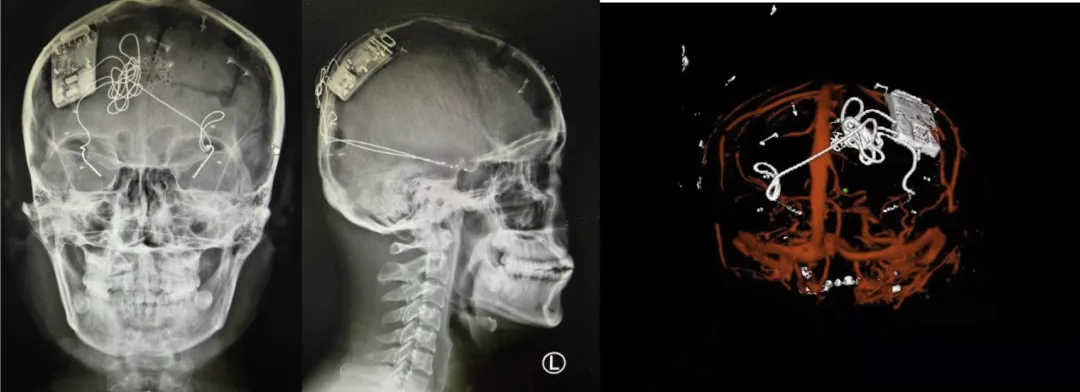

中国首例“脑机接口”反应性闭环神经刺激系统植入成功

据介绍,3月9日,首都医科大学宣武医院院长赵国光教授、神经外科单永治教授带领的神经外科立体定向与功能性脑疾病组团队成功为一名难治性癫痫患者施行了闭环反应性神经刺激系统Epilcure™注册临床试验植入手术,术后重建显示电极位置精准,脑电信号清晰。闭环反应性神经刺激系统为“脑机接口”在临床领域的重要应用,该技术通过将人工智能芯片植入颅骨,颅内电极植入脑内,昼夜无间断监测脑电节律,一旦预测到即将发生的癫痫,即启动外源性干扰节律,直接阻断致痫灶内的癫痫形成,精准的控制环路的活动。